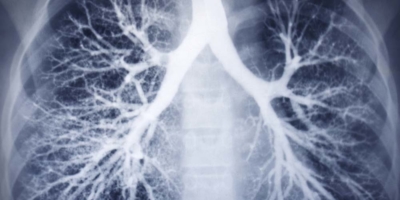

Are Your Lungs Shrinking?

When it comes to physical health, there are few things more important than “lung power.” Great martial artists like Bruce Lee knew physical strength and robust health depend on your lungs. The strong men of my father’s era knew it too. Part of what gives you the capacity to live robustly is getting enough oxygen. [...]